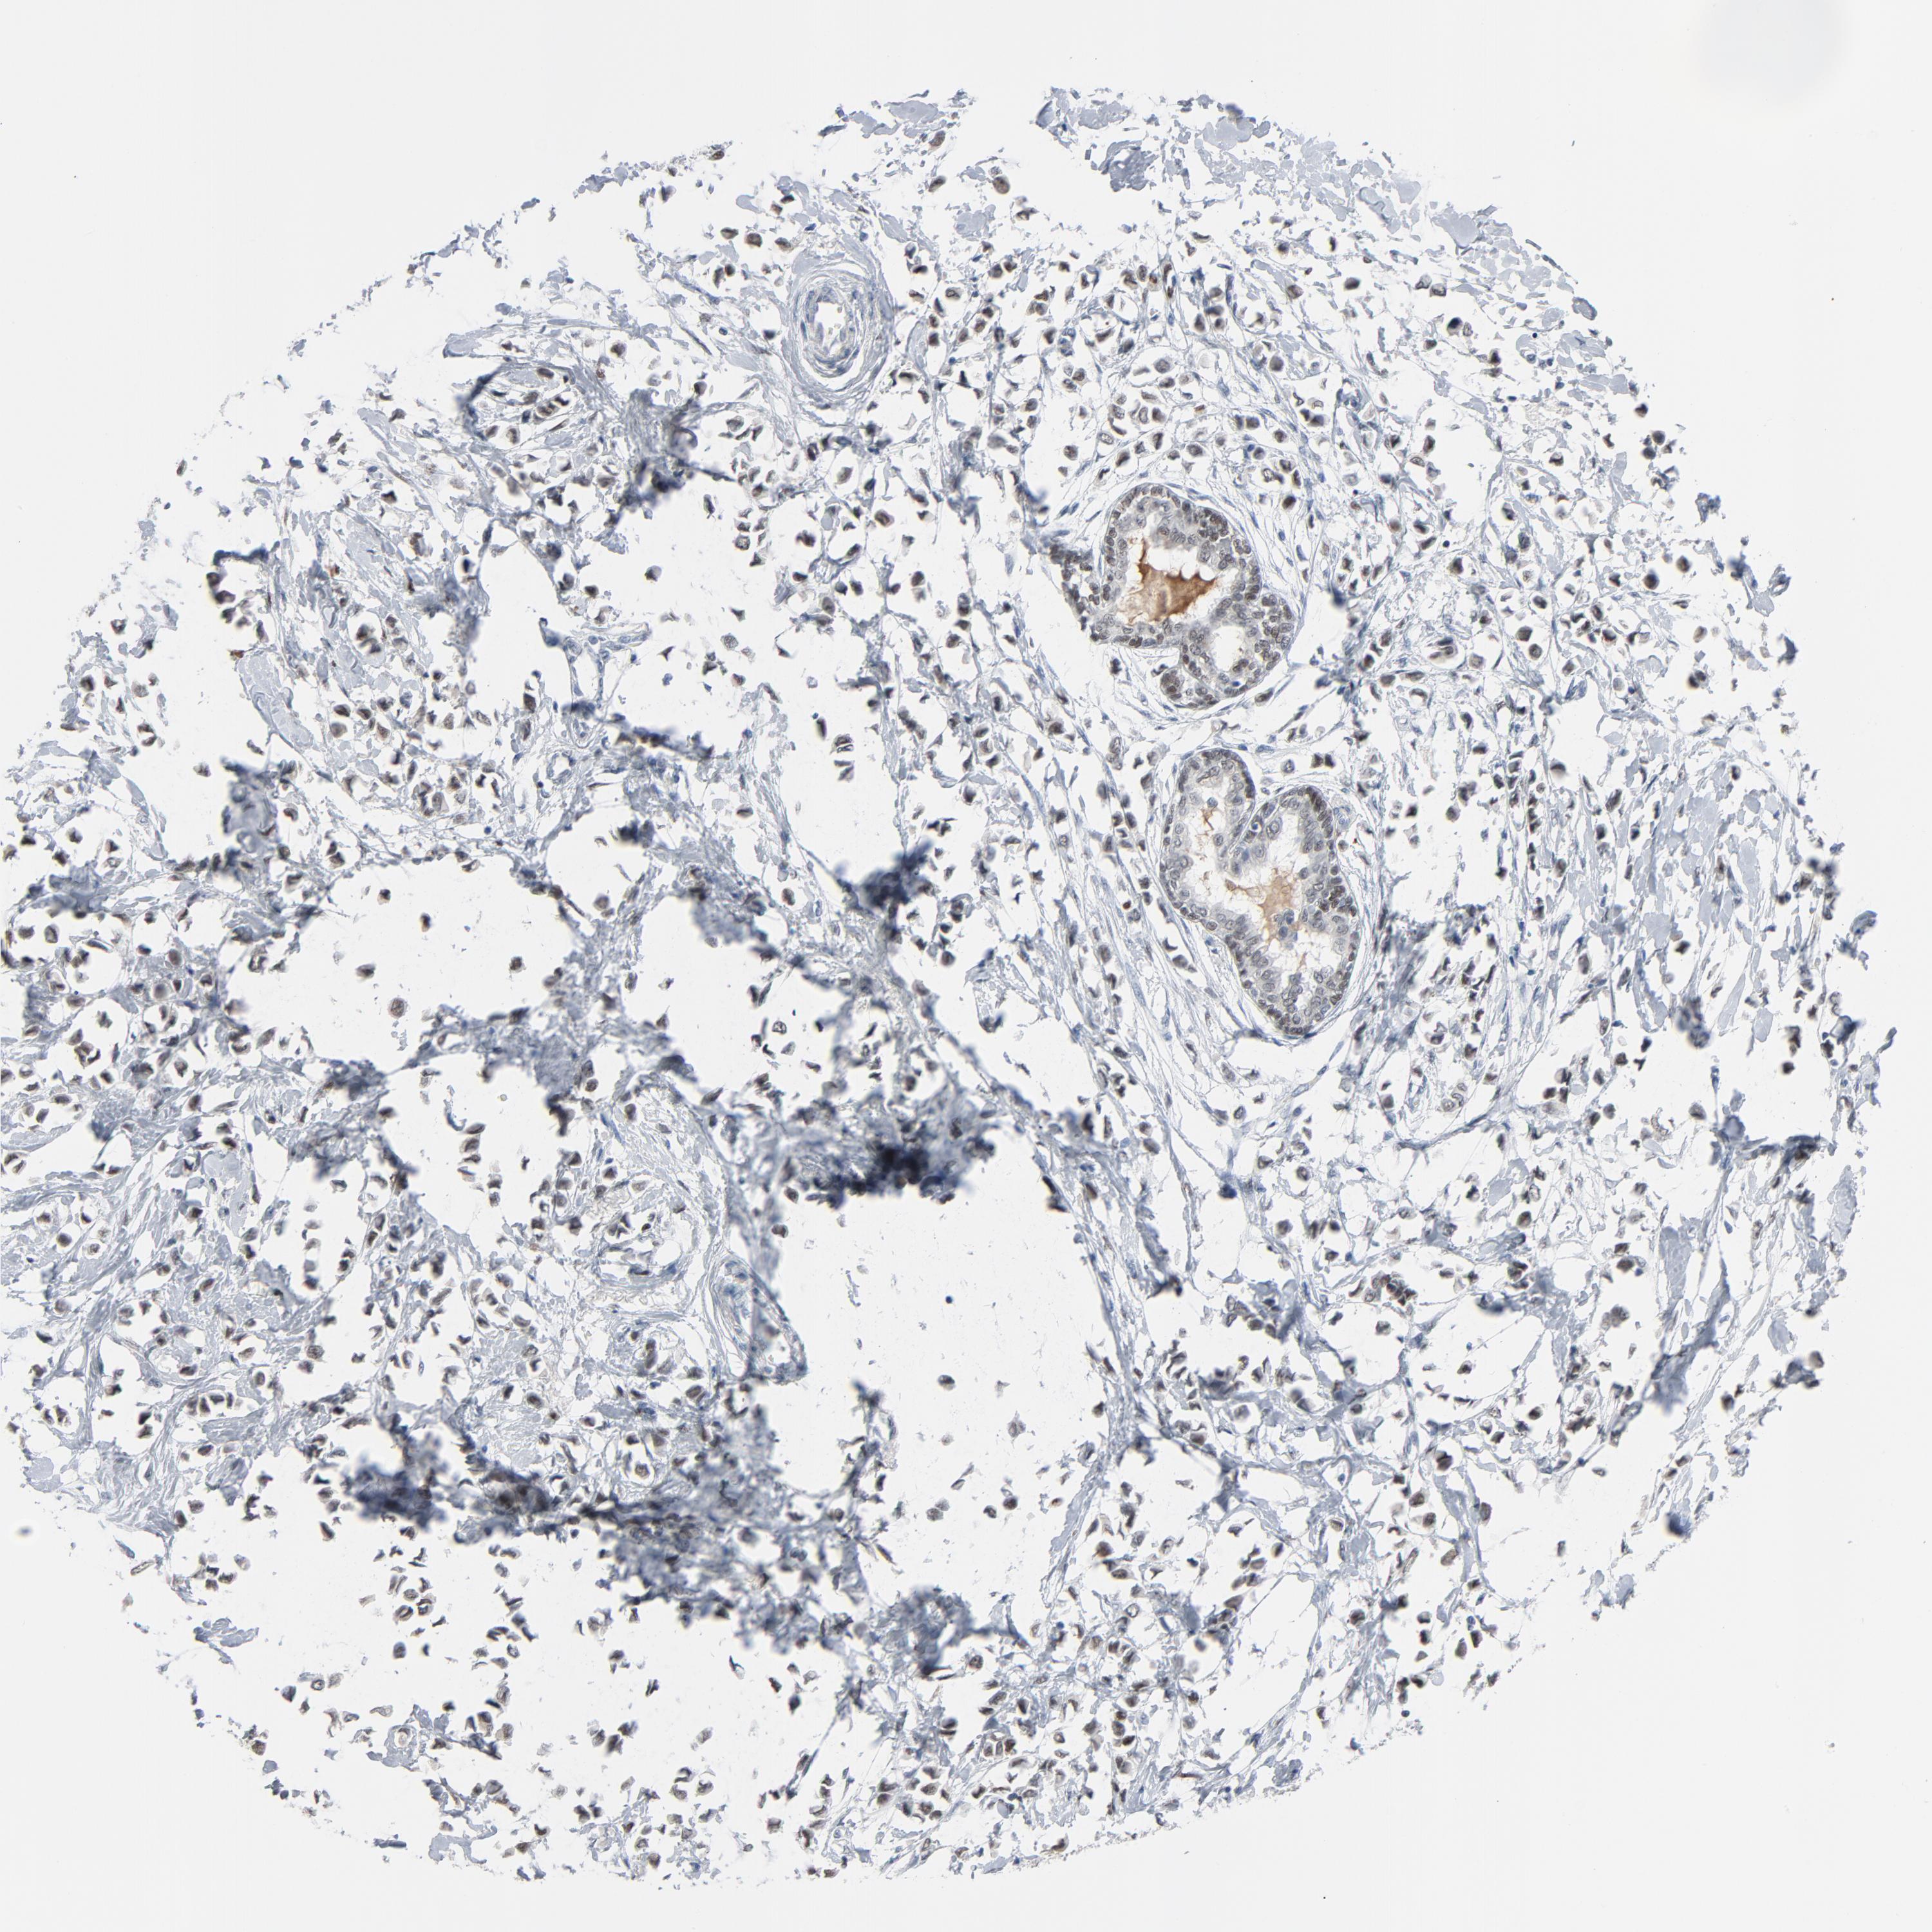

BRCA TCGA BRCA VALIDATION PROTEIN EXPRESSION

ANTIBODIES

AND

VALIDATION